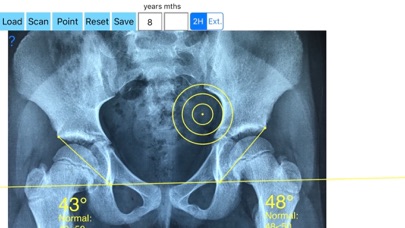

The diagnosis of hip dysplasia, the prognosis, the evaluation of different methods of treatment is based mainly on X-rays of the hip joint. For the objective evaluation of hip dysplasia in  everyday orthopaedic care the  acetabular index (AI) or the Centre-edge angle (CE) are frequent measured. But the measurement of AI is not valid index for acetabular Dysplasia in children  over 8 years of age and in cases with subluxation of the femoral head where the centre-edge angle (CE) is  not accurately calculated. The acetabular angle of Sharp (AA) is especially designed for theses cases. The acetabular angle of Sharp (AA) is formed by a horizontal line connecting the tips of the both pelvic teardrops and by a line connecting the inferior tip of the pelvic teardrop with the most lateral point of the acetabular roof.

-Offers a very convenient way to determine the most accurate possibly lines in order to measure the angles. By the aid of a circular transparent template, the points of interest are marked accurately. The automatically formed lines, drawn between points, measure automatically the angles of interest. The results are printed in degrees. By inputing the age, of the patient in the App, the measured angle is compared with values from normal reference database  according  to patient age. In case the measured angle is beyond the normal range for that age, the hips are categorised as borderline dysplastic or dysplastic.

The app is a handy tool for an orthopaedic surgeon, radiologist, medical student or resident who wants objectively  monitor and determine the severity of dysplasia of the hip. The build-in comparison feature with the normal reference values according to patient age may help decide what could be considered normal or borderline dysplastic or dysplastic. The app is not a simple goniometer, is an enhanced product which offers the ability to compare all the input data with medical reference database. The results are printed on the screen and the hips are categorised as normal or dysplastic  according to the AA angle measures respectively. This feature  it is particular useful especially in clinical settings where you need a quick results without losing time in looking for reference data according to age variations in huge textbooks.